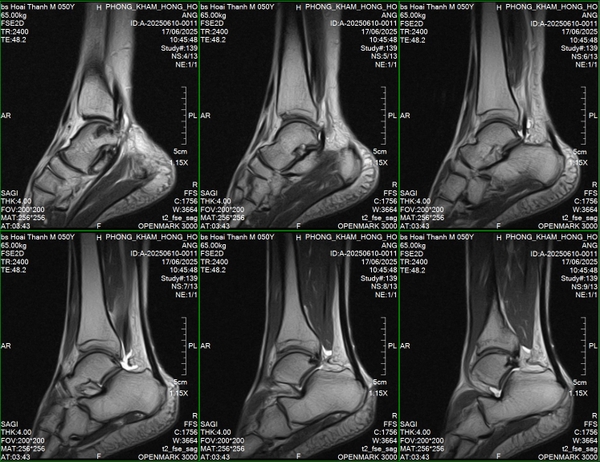

🌿Mới đây, Phòng khám đa khoa Hồng Hoàng đã lắp đặt xong hệ thống chụp cộng hưởng từ OPENMARK III – 0.3 Tesla, sau đó tiếp tục được đào tạo và chuyển giao công nghệ từ sự hỗ trợ của các kỹ thuật viên trong nước và nước ngoài.

🐟𝐌𝐑𝐈 𝟎.𝟑𝐓 𝐎𝐏𝐄𝐍𝐌𝐀𝐑𝐊 𝐈𝐈𝐈 – là hệ thống từ trường thấp, nhưng với thiết kế tối ưu, có chất lượng cao và phần mềm xử lý hình ảnh thông minh, hoàn toàn có khả năng chẩn đoán chính xác các nhóm bệnh lý sau:

🔹𝐂𝐨̛ 𝐱𝐮̛𝐨̛𝐧𝐠 𝐤𝐡𝐨̛́𝐩: phát hiện rách gân cơ, viêm khớp, tổn thương sụn – dây chằng – thoái hóa khớp.

🔶Hình ảnh đầu ra rõ nét, hỗ trợ bác sĩ đưa ra quyết định lâm sàng nhanh chóng và chính xác.